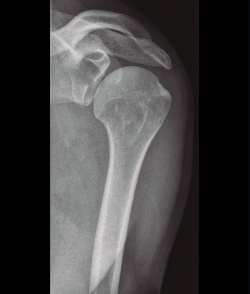

Shekelle et al.(9) concluyen que no existe evidencia en cuanto a la elección del tipo de tratamiento, pero sí resulta de gran importancia individualizar el tratamiento valorando de forma integral al paciente, considerando el grado de desplazamiento, la densidad ósea, la edad y las lesiones asociadas (Figura 5).

Figura 5. Radiografía simple de fractura del húmero proximal.